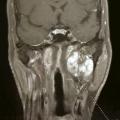

L’IRM est l’examen de référence. Elle permet de mettre en évidence des tumeurs de petite taille, d’affirmer la nature paro­tidienne de la masse et parfois de localiser le nerf facial par rapport à la tumeur. Elle offre en outre une orientation diagnostique (séquences de perfusion-diffusion) :

• adénome pléomorphe : hypersignal T2, polylobé, unifocal ;

• cystadénolymphome : kystique, multifocal, régulier ;

• tumeur maligne (carcinome adénoïde kystique) : masse infiltrante à limites irrégulières.